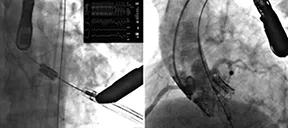

Patients Overall Health is Key to Aortic Valve Procedure Outcome

Study: Cardiac Resynchronization Therapy Best to Treat Heart Block